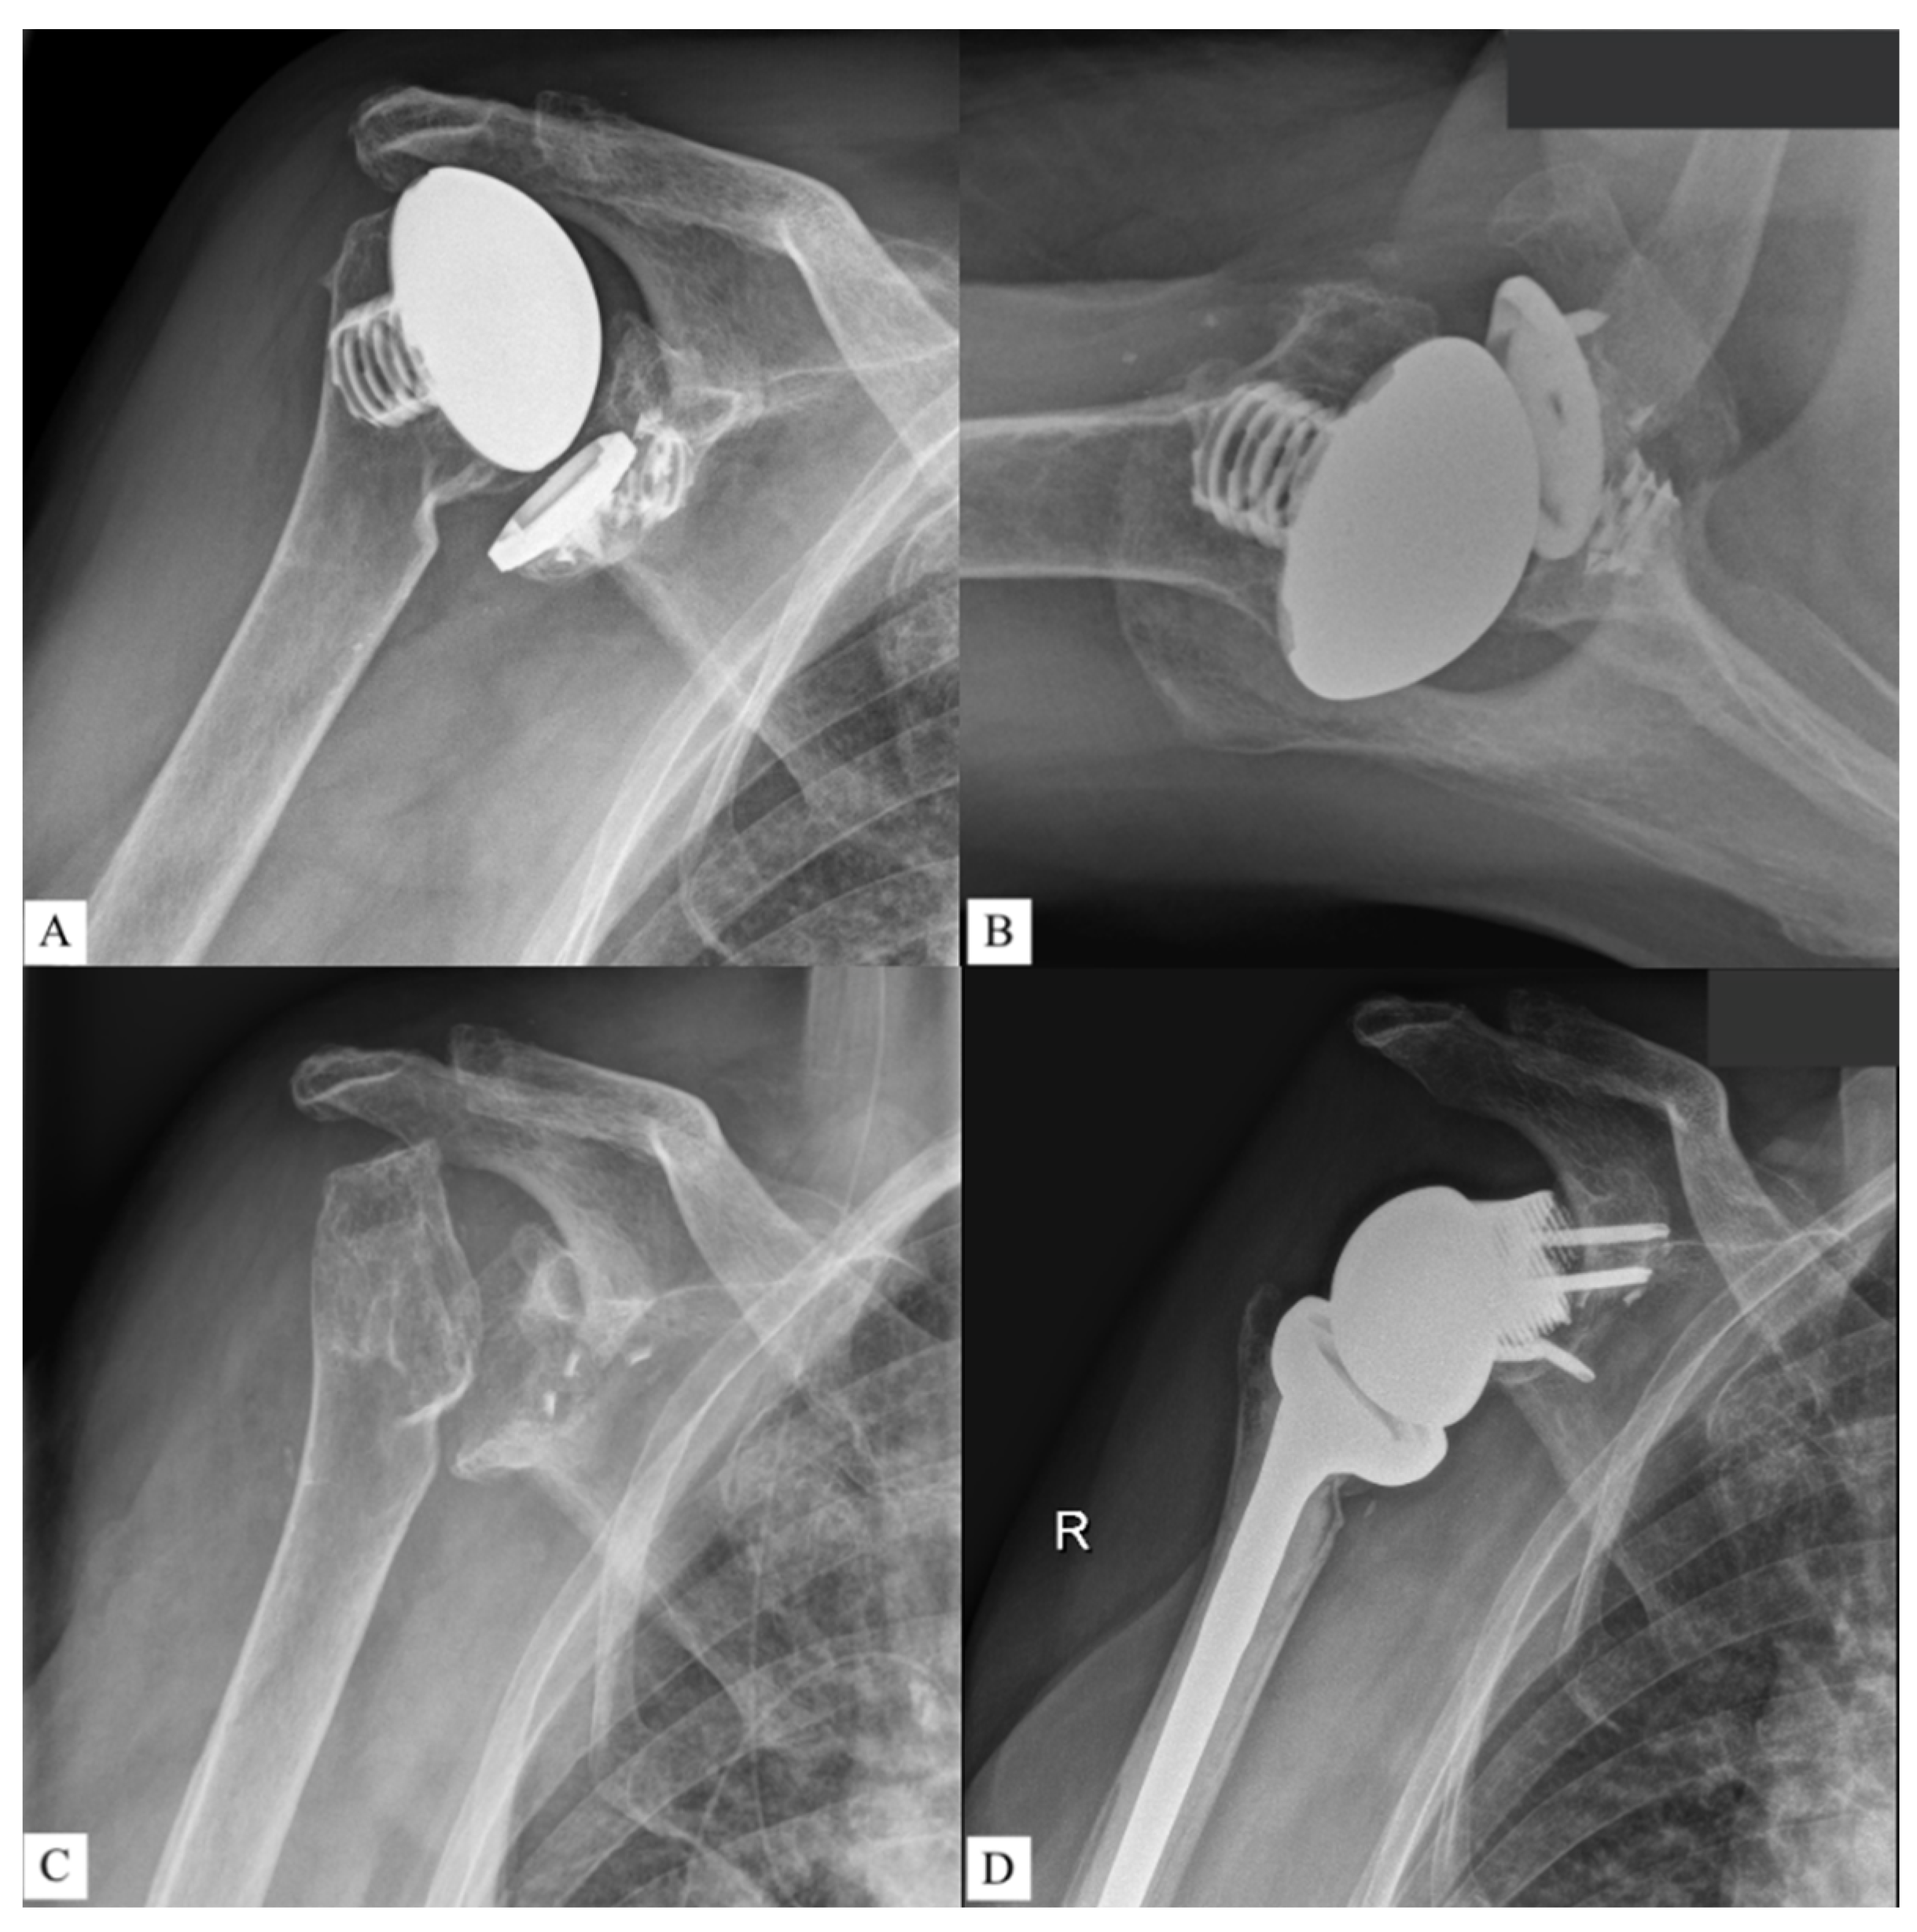

Finally, no complications were observed during surgery or in follow-up. Figure 4 and Figure 5 show two patients who received revision rTSA. The patients are very happy with the outcome. Considering the devastating initial situation, the comparison between preoperative X-rays and postoperative X-rays shows an excellent result.

Figure 5. Third case of a revision rTSA. The preoperative situation is displayed in the images on the top (A,B). The bottom images show the outcome in AP (C) and lateral direction (D). Reprinted with permission from Materialise. ©2021 Materialise NV.